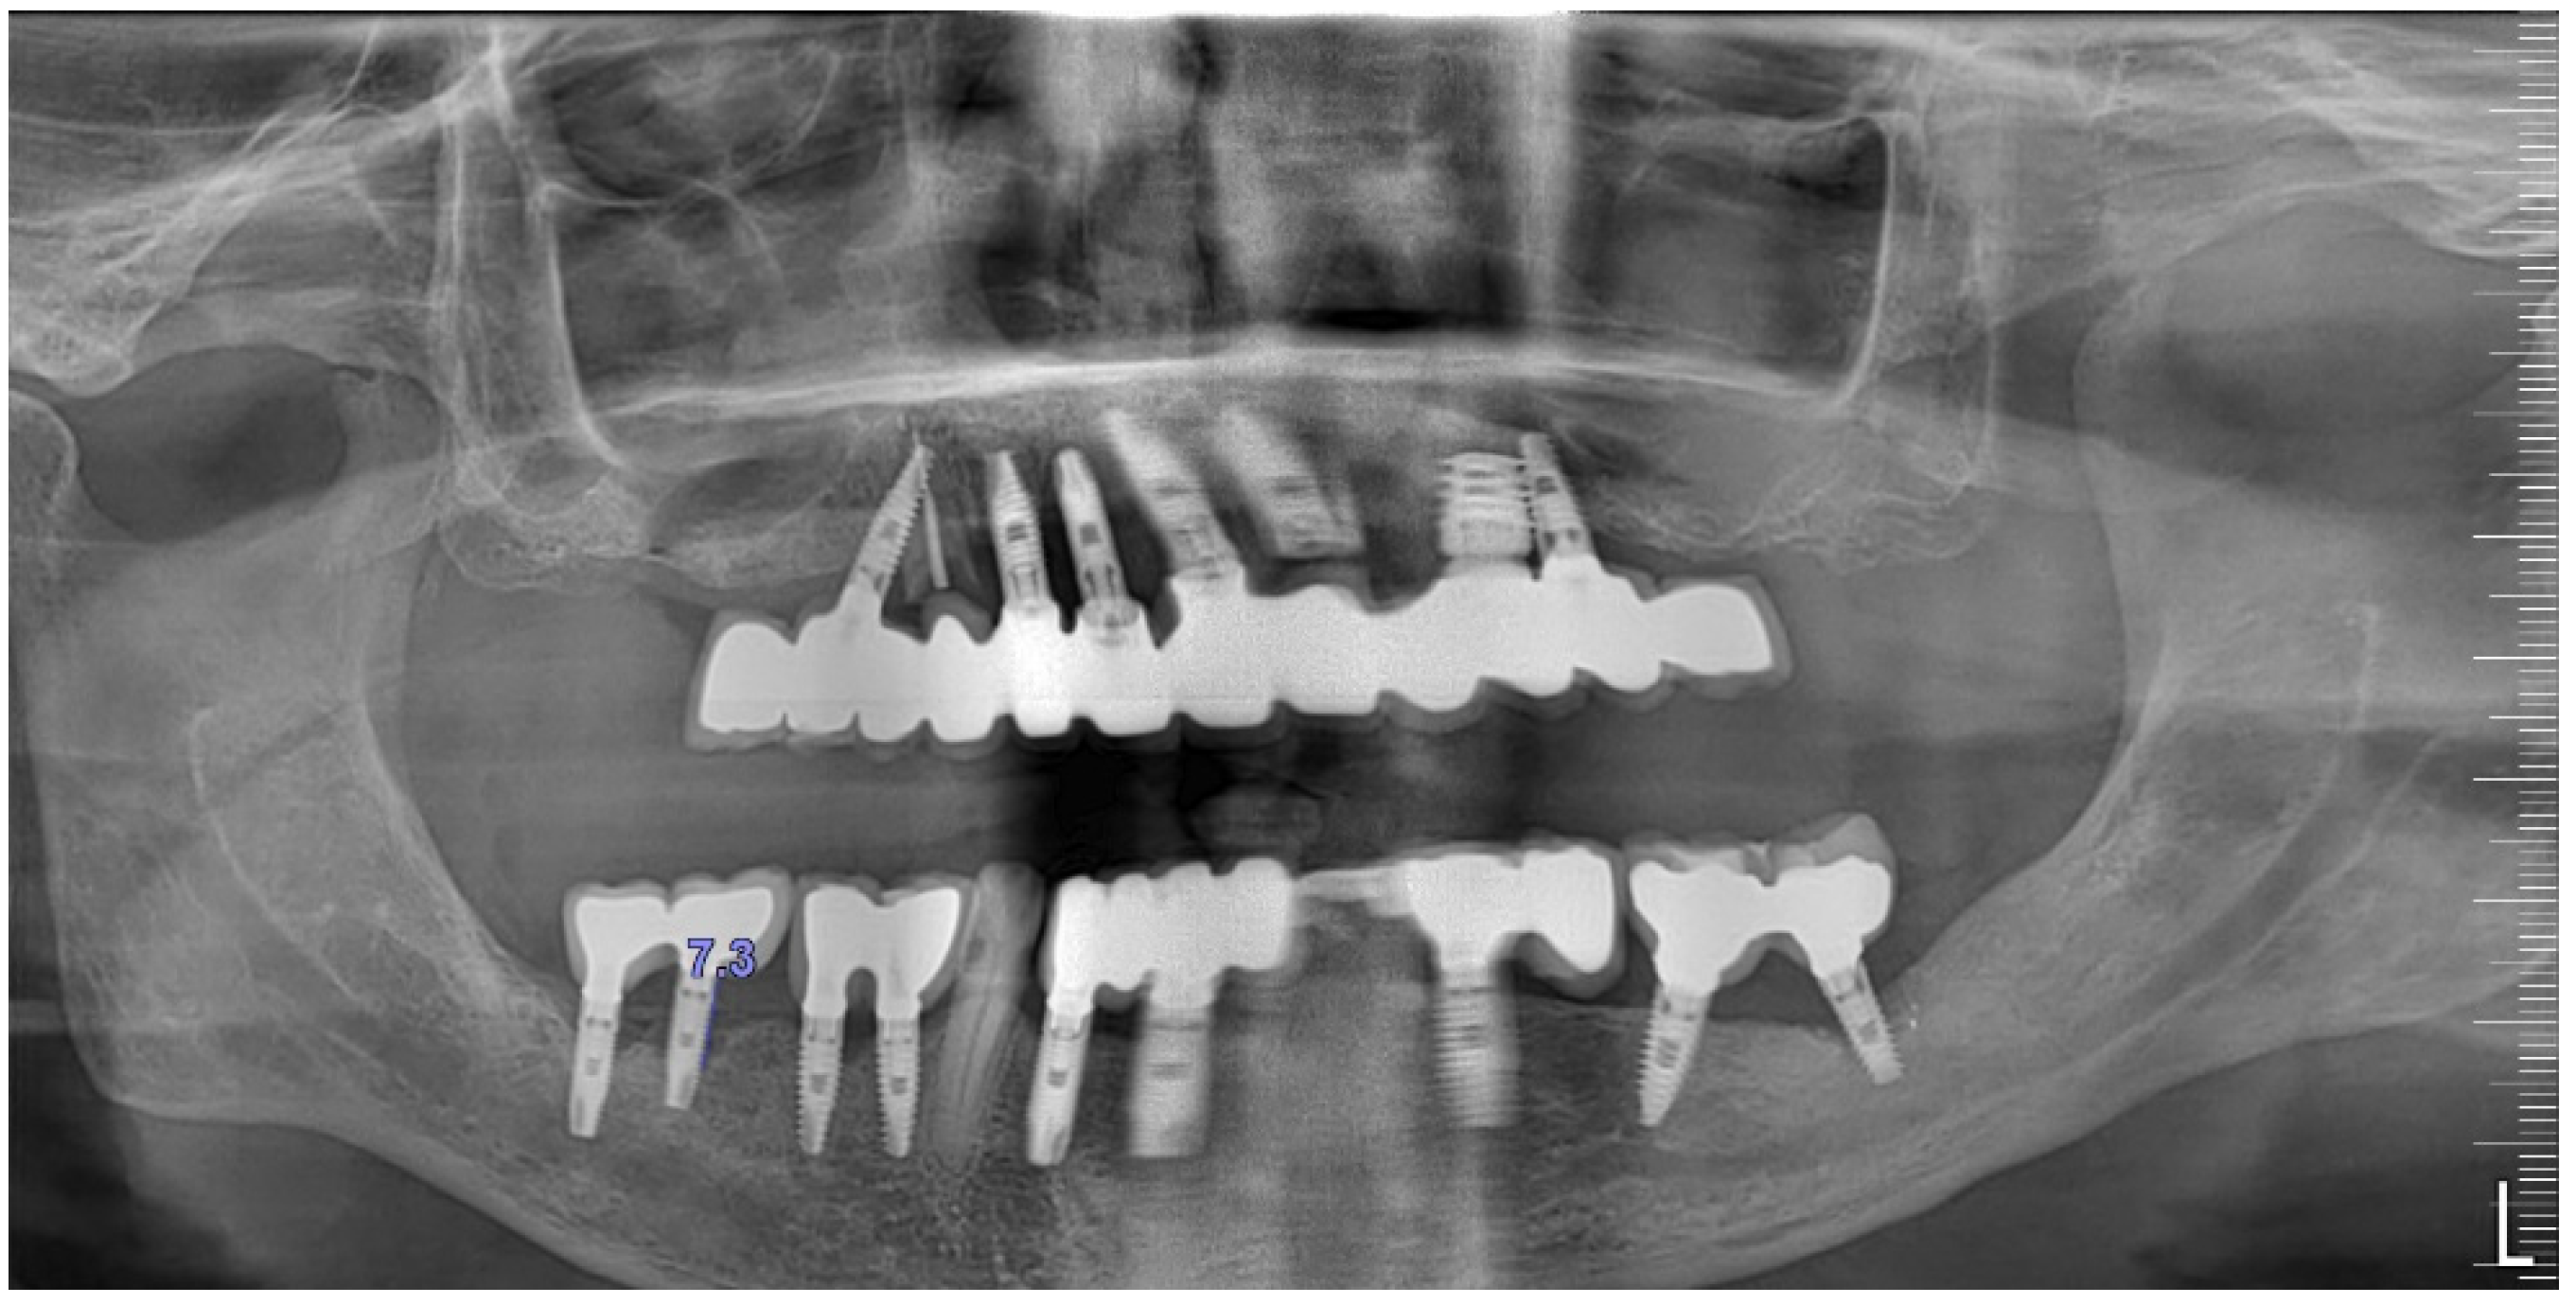

The intraoral examination revealed poor oral hygiene, characterized by significant plaque accumulation (over 65% plaque index) along the gingival margins and interdental areas. The periodontal status evidenced a progressive periodontal disease, with bleeding on probing (BoP) over 60%, mainly around all dental implants; peri-implant tissues possessed a high level of inflammatory condition, with localized swelling, high level of BoP, redness, and suppuration at the site of teeth #46 and #47, indicating local acute inflammation. The probing depth (PD) at site implant #46 exceeded 9 mm at both the mesial and distal sites, and at #47, the mesial site had a PD of 7.8mm, while the distal site showed lower bone loss (Figure 7).

Radiographically (Figure 8), the findings demonstrated full mouth edentulism, rehabilitated with upper and lower bridges and crowns supported by dental implants, as well as bone loss at #37, #46, and #47. The peri-apical radiograph (Figure 7) showed two dental implants, each measuring 13 mm, with bone loss around implant #46 (exceeding 60% of the implant length) and around implant #47 (exceeding 70% of the implant length).

Figure 8. The initial panoramic radiograph reveals oral rehabilitation and bone loss in the lower posterior teeth.